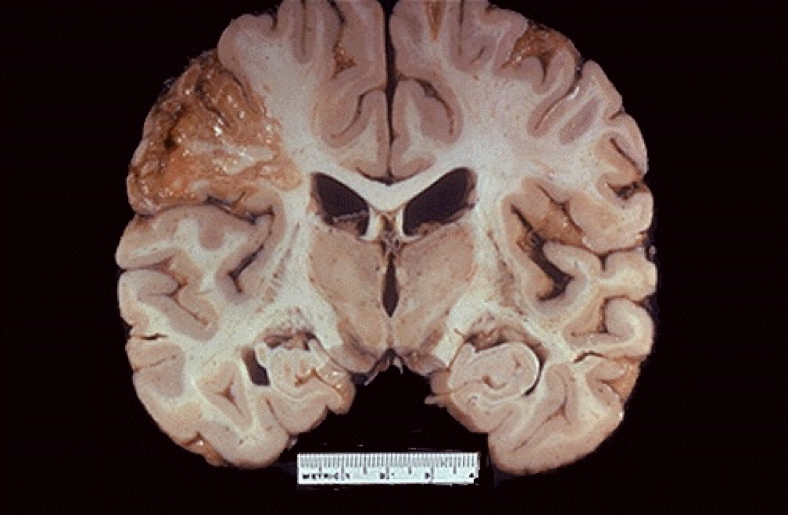

Liquefactive Necrosis

- Enzymatic digestion dominates

- Pus formation, abscess

- Also seen in CNS infarcts